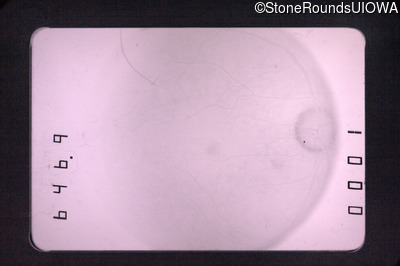

Fluorescein Angiography - Left - 20/400

Exemplar